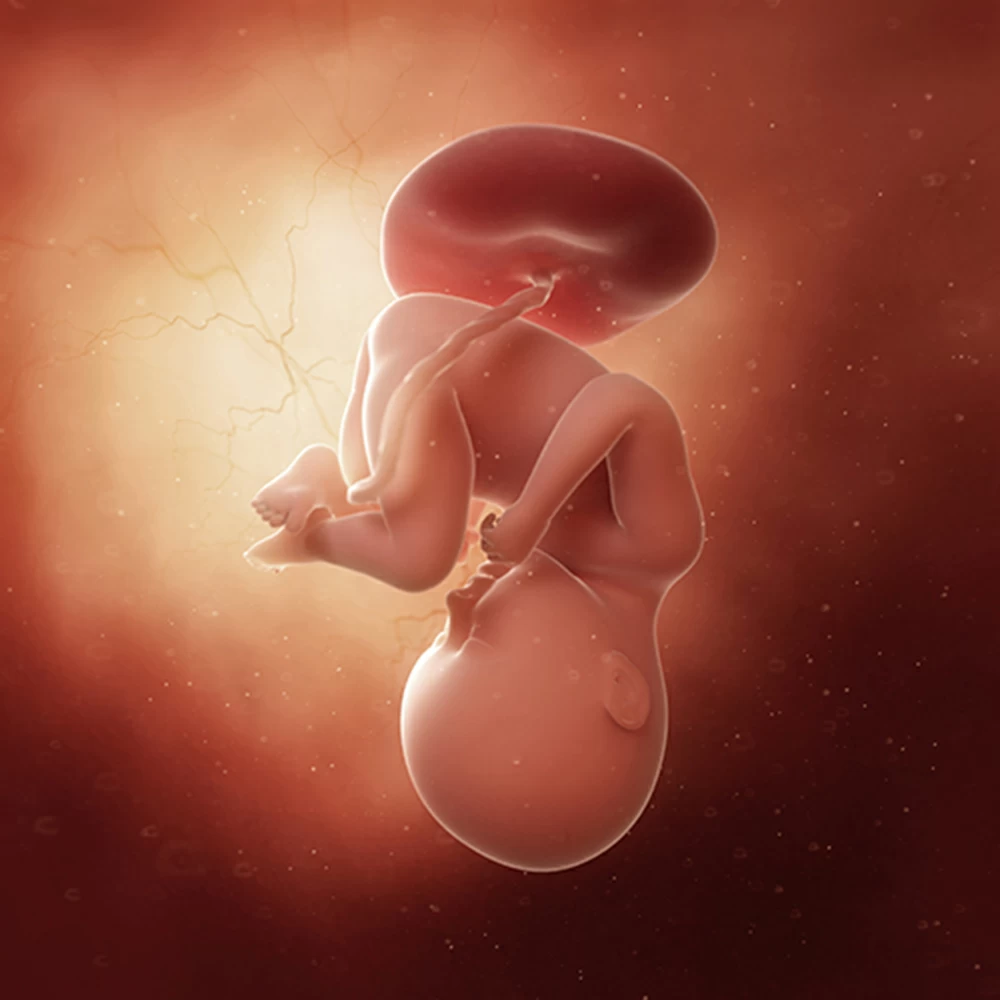

Неделя № 7

Седьмая неделя знаменательна тем, что окончательно завершается формирование пуповины и устанавливается маточно-плацентарное кровообращение. Теперь дыхание и питание плода будет осуществляться за счет циркуляции крови по сосудам пуповины и плаценты.

Эмбрион согнут еще дугообразно, на тазовой части тела имеется маленький хвостик. Размер головы составляет не менее всей половины зародыша. Длина от темени до крестца к концу недели вырастает до 13-15 мм.